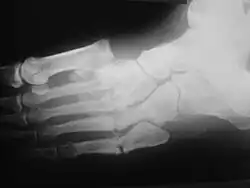

Диабети́ческая о́стеоа́ртропати́я

Является одним из тяжёлых осложнений, вызывающих стойкую потерю трудоспособности пациентов, нередко молодого возраста. Развивается у лиц с длительно некомпенсированным, лабильно текущим инсулинозависимым сахарным диабетом. Частота диабетической остеоартропатии (специфического поражения костей и суставов) колеблется от 5 до 23% всех случаев сахарного диабета[1]. Ведущая роль в патогенезе принадлежит диабети́ческой нейропати́и в сочетании с нарушениями микроциркуляции и метаболизма, приводящим к ишемическим некрозам. Клиническая картина аналогична другим нейрогенным остеоартропатиям. Локализация процесса — обычно дистальные мета́физы метатарза́льных косте́й и проксимальных мета́физах стоп, реже в процесс вовлекаются коленные и лу́чезапя́стные суставы. Изменения носят характер одностороннего поражения, редко симметричны. Сустав отёчный, безболезненный, гиперемия отсутствует, кожа холодна на ощупь. Рентгенологическая картина: изменение суставных поверхностей косте́й в виде остеопоро́за, остео́лиза, остеосклеро́за, внутрисуставных переломов, со временем развивается деформация сустава. Присоединяющаяся инфекция приводит к перифокальной гнойнонекротической реакции мягких тканей и остеомиелиту, возникают трофические язвы и свищи.